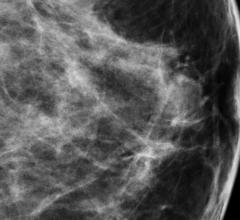

Mammography is a breast imaging technique that uses X-rays to diagnose and locate tumors of the breasts.

Despite decades of progress in breast imaging, one challenge continues to test even the most skilled radiologists ...